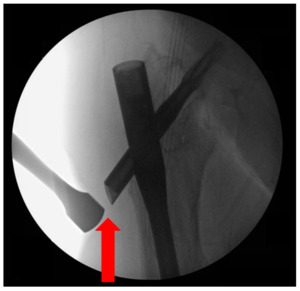

The patient is placed on a radiolucent Jackson flat top table with a beanbag to facilitate a “sloppy lateral” position. The entire operative extremity is prepped and draped independently of the well leg, allowing the surgeon to assess a full range of motion following TFL and ITB excision. Intra-operative fluoroscopy is used to localize the appropriate starting point for the incision at the lateral end of the PLD, while utilizing previous surgical scars. (Figure 1)